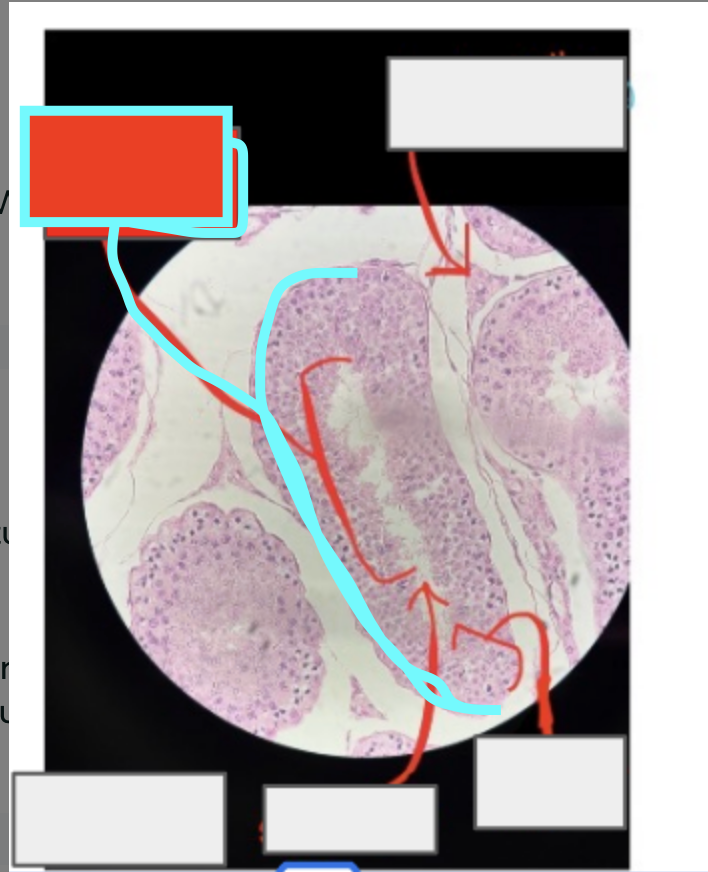

Uterus

What organ is this?

Myometrium

Endometrium

Endometrial glands

simple columnar epithelium

What is this?

What type of tissue would you find here?